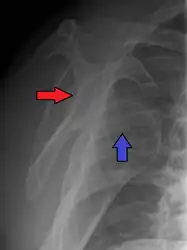

Posterior (backward)

Posterior dislocations are uncommon, and are typically due to the muscle contraction from electric shock or seizure.[5] They may be caused by strength imbalance of the rotator cuff muscles. People with dislocated shoulders typically present holding their arm internally rotated and adducted, and exhibiting flattening of the anterior shoulder with a prominent coracoid process.

Posterior dislocations may go unrecognized, especially in an elderly person[11] and in people who are in the state of unconscious trauma.[12] An average interval of 1 year was noted between injury and diagnosis in a series of 40 people.[13]

Lightbulb sign indicative of posterior shoulder dislocation shown on the left. On the right, the same shoulder after reduction. -

Axillary view of the left shoulder showing a posterior dislocation